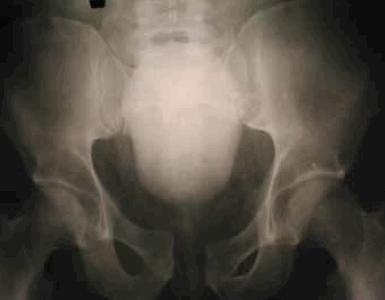

Рисунок 4. Рентгенограммы и компьютерная 3D-реконструкция таза пациента К. 19 лет, повреждение тазового кольца 61-В2: a) рентгенограмма таза до операции; b) рентгенограмма после остеосинтеза винтами переднего и заднего комплексов таза; c) 3D-реконструкция таза до операции; d) 3D-реконструкция таза после остеосинтеза переднего и заднего комплексов